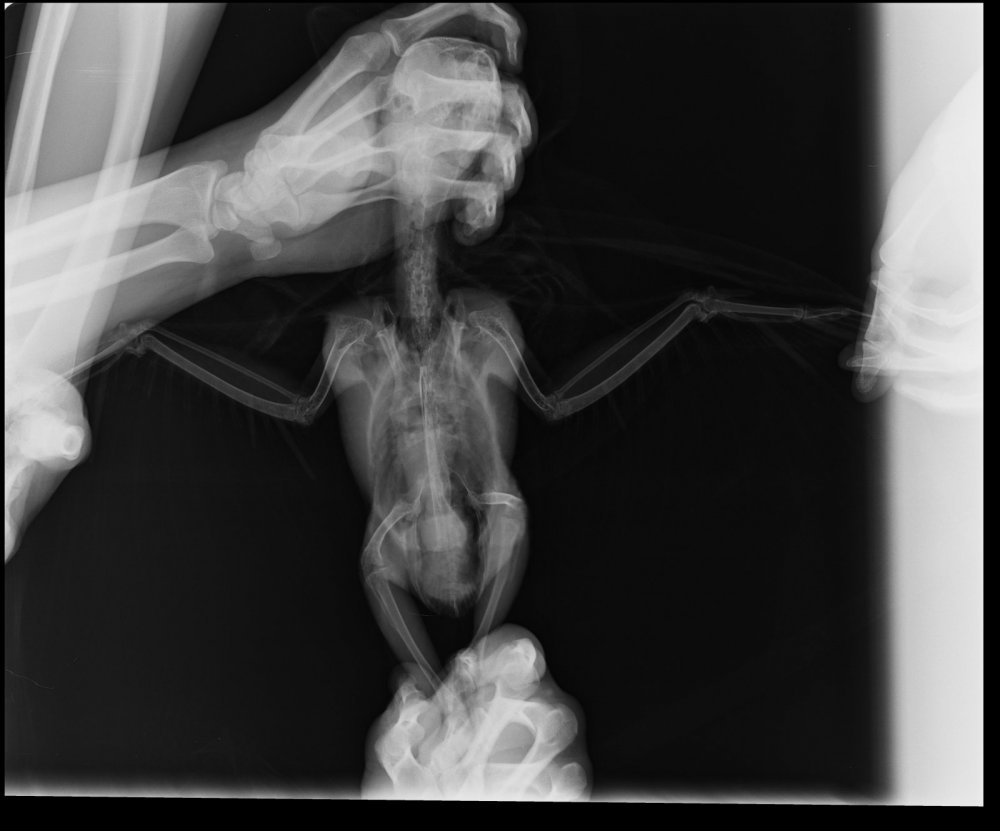

11 декабря сдали анализы. Результаты анализов прикрепила к данному сообщению, а также рентген.

Рентген: очаговые затемнения в легких, затемнен правый брюшной воздушный мешок

Кардтомегалия: увеличен железистый желудок

Диагноз: бронхопневмония, аэросаккулит, кардиопатия